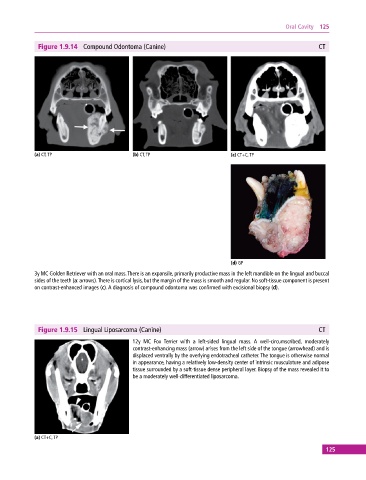

Figure 1.9.14 Compound Odontoma (Canine) CT

(a) CT, TP (b) CT, TP (c) CT+C, TP

(d) GP

3y MC Golden Retriever with an oral mass. There is an expansile, primarily productive mass in the left mandible on the lingual and buccal

sides of the teeth (a: arrows). There is cortical lysis, but the margin of the mass is smooth and regular. No soft‐tissue component is present

on contrast‐enhanced images (c). A diagnosis of compound odontoma was confirmed with excisional biopsy (d).

Figure 1.9.15 Lingual Liposarcoma (Canine) CT

12y MC Fox Terrier with a left‐sided lingual mass. A well‐circumscribed, moderately

contrast‐enhancing mass (arrow) arises from the left side of the tongue (arrowhead) and is

displaced ventrally by the overlying endotracheal catheter. The tongue is otherwise normal

in appearance, having a relatively low‐density center of intrinsic musculature and adipose

tissue surrounded by a soft‐tissue dense peripheral layer. Biopsy of the mass revealed it to

be a moderately well‐differentiated liposarcoma.

(a) CT+C, TP